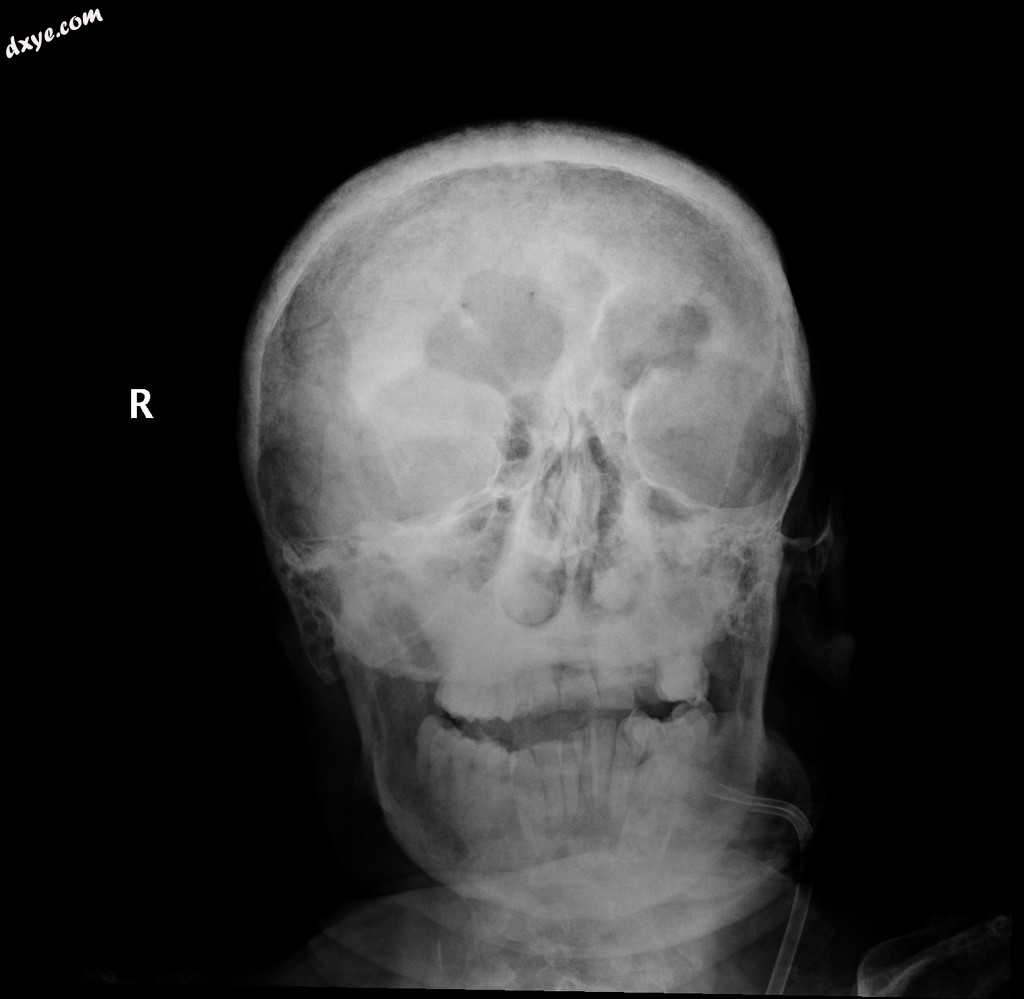

X射线

5.jpeg

正位

颅骨穹窿呈弥漫性增厚,伴有多发性小的溶解性病变,可能是由于甲状旁腺功能亢进所致,不太可能是多发性骨髓瘤。

结果是由于甲状旁腺功能亢进。

这位50岁的先生因患有慢性肾功能衰竭,入院时接受了我们医院的permcath插入术,接受透析治疗。最初,他的主治医生要求进行甲状腺超声检查,结果显示由于长期低钙血症,甲状旁腺增生。胸部X光检查显示侧锁骨软骨下吸收,无气胸迹象。头骨及双腕X线片显示多个微小透明的颅骨穹窿病变、软组织钙化、骨脱钙、肋骨切口和肢端骨溶解,所有这些都是由于继发性甲状旁腺功能亢进所致。